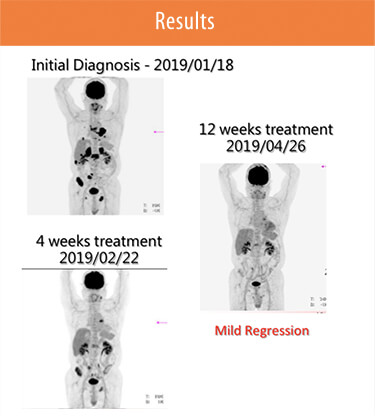

User Story #2

Patients with Lung Cancer Due to Exon 19 mutation in EGFR